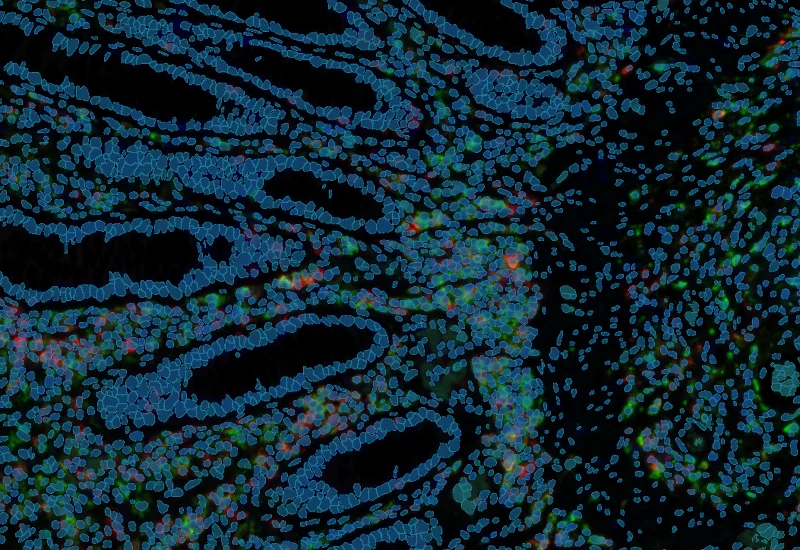

Analyze single-cell co-expression of three IF markers, segment cells into nucleus, perinuclear area, and/or cytoplasm, and export up to 20 intensity, statistic, and morphometric parameters per compartment.

The IF 3 App provides single cell based co-expression analysis for three IF markers. It segments cells into nucleus, and/or perinuclear area and/or cytoplasm. Each segmented cell compartment is measured for up to 20 intensity, statistic and morphometric parameters which can be displayed in scattergrams and histograms and exported.

Co-Expression